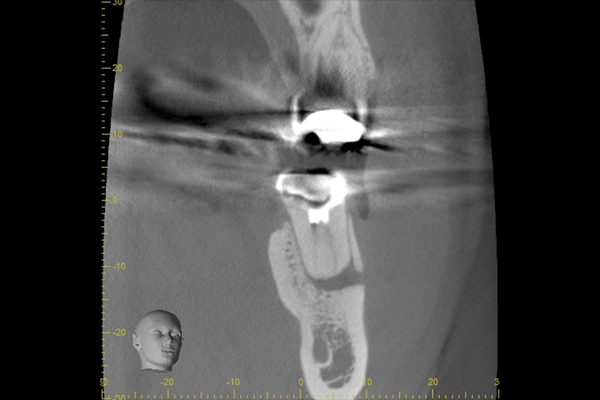

| 根の中にお薬を充填した後のCT画像。やはり根の先に黒い影があるのがわかります。 |

| 根の先の黒い影は消失しました。 | 術後6ヶ月のCT画像です。こちらでも、根の先に黒い影は見当たらないです。 |

患歯を見極めるためと、状態の悪さをみるため、CTを撮影しました。治療前では上顎洞への大きな炎症が見られます。また、上顎洞底線も無くなっています。また左上の前から4番目の歯の根尖周囲にも透過像が見られます。5番目の歯に関しては根尖が鋭利になっており、根尖性歯周炎によって吸収されたことがわかります。ですので、まず第一の患歯は5番目の歯であるとしました。

治療後3ヶ月経つと上顎洞への炎症も無くなっています。また、上顎洞底線もきれいにみえます。4番目の歯の根尖周囲の透過像もなくなりました。5番目の根尖にまだ透過像がありますが、臨床的症状がないことから、治癒傾向にあるものと判断しました。